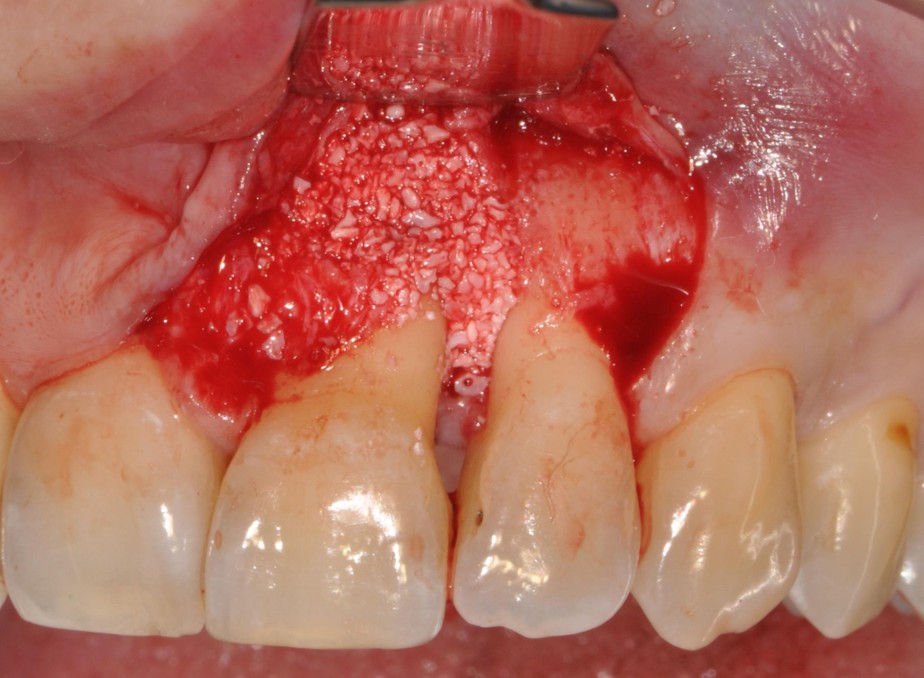

This workshop will explore the biological rationale, clinical decision-making, and surgical techniques involved in periodontal regeneration. While the primary focus will be on the regenerative management of infrabony defects, the discussion will be extended to more complex defect configurations. Particular emphasis will be placed on defect morphology, as well as on the selection of biomaterials and surgical approaches that critically influence clinical outcomes.

Key topics will include flap design, papilla preservation strategies, wound stability, soft tissue management, post-operative care, as well as the limitations and challenges of periodontal regeneration. Even in complex periodontal defects, a sound biological and clinical rationale for reconstruction and regeneration can often be identified.

The workshop will therefore highlight the importance of minimally invasive surgical concepts and appropriate biomaterial selection as critical factors in the successful management of advanced and complex periodontal defects. Ultimately, the aim of this workshop is to equip clinicians with practical tools and a structured clinical framework to apply regenerative concepts in a predictable manner, thereby maximizing long-term tooth retention and periodontal stability.